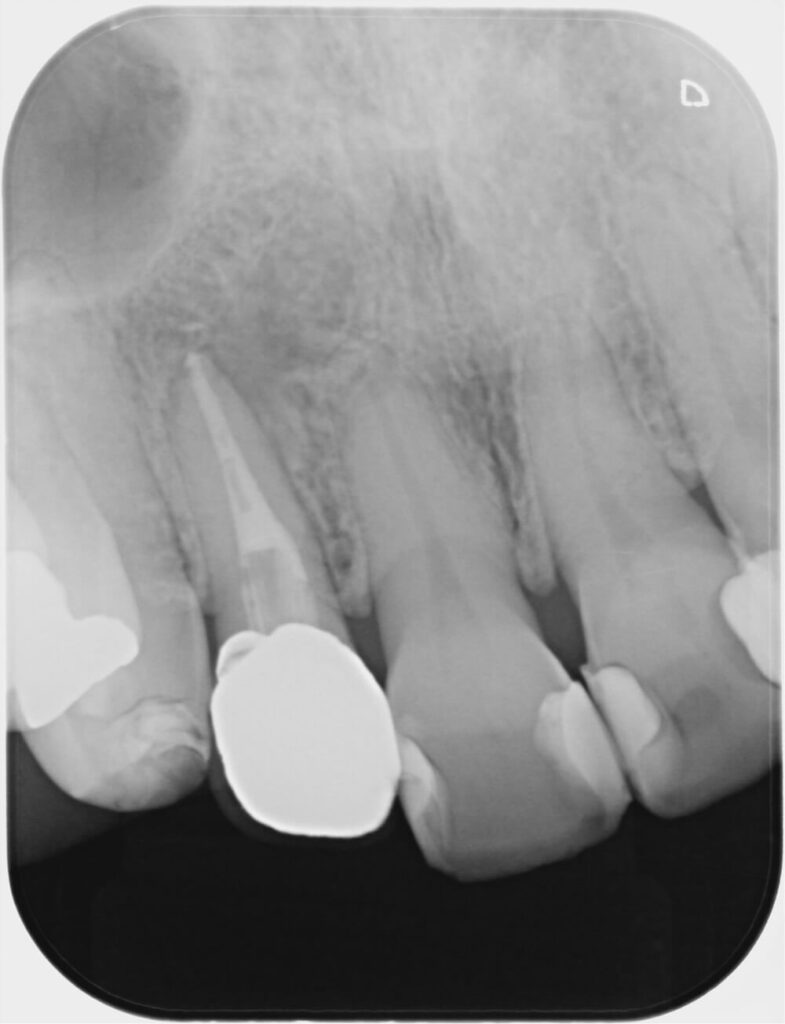

■術前→ 1年6か月後の変化

初診時(左) 1年6か月後(右)

2年後の再評価では、

- 痛みなし

- 腫れなし

- 日常生活でも快適に機能

- レントゲン上で骨の改善確認

と、とても良好な状態でした。